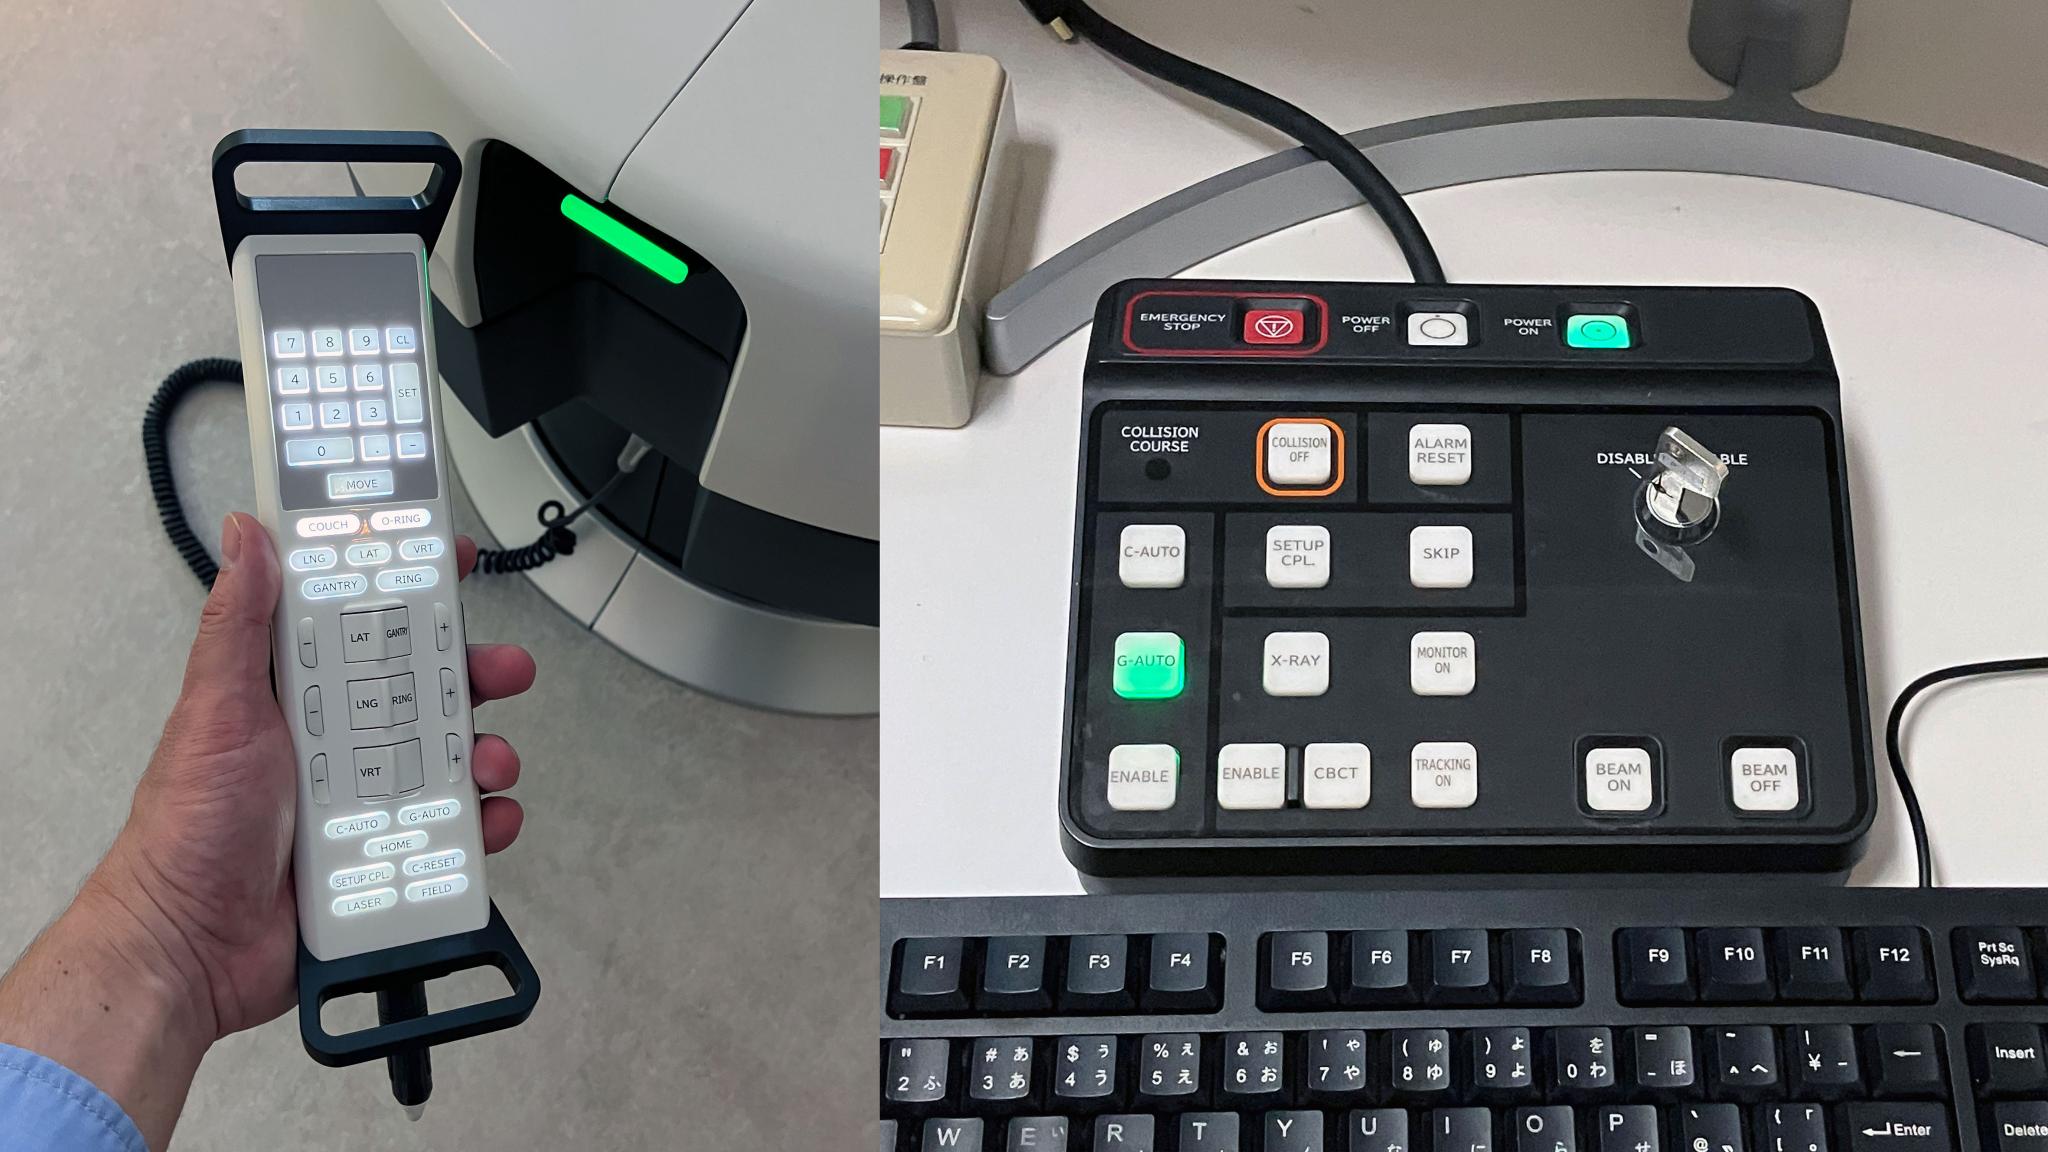

Hitachi High-Tech, Ltd.The OXRAY is a cancer treatment system in which the stage and the inside of the gantry rotate on two axes to deliver X-rays from various angles. The gimbal function enables dynamic tracking of cancer tissue that moves with respiration, which reduces the physical burden and enables high-precision treatment. This reduces side effects and treatment time. In addition, the irradiation range has been expanded to accommodate more cases, and throughput has been significantly improved by integrating individual systems. As of 2025, the system will be available only in Japan.